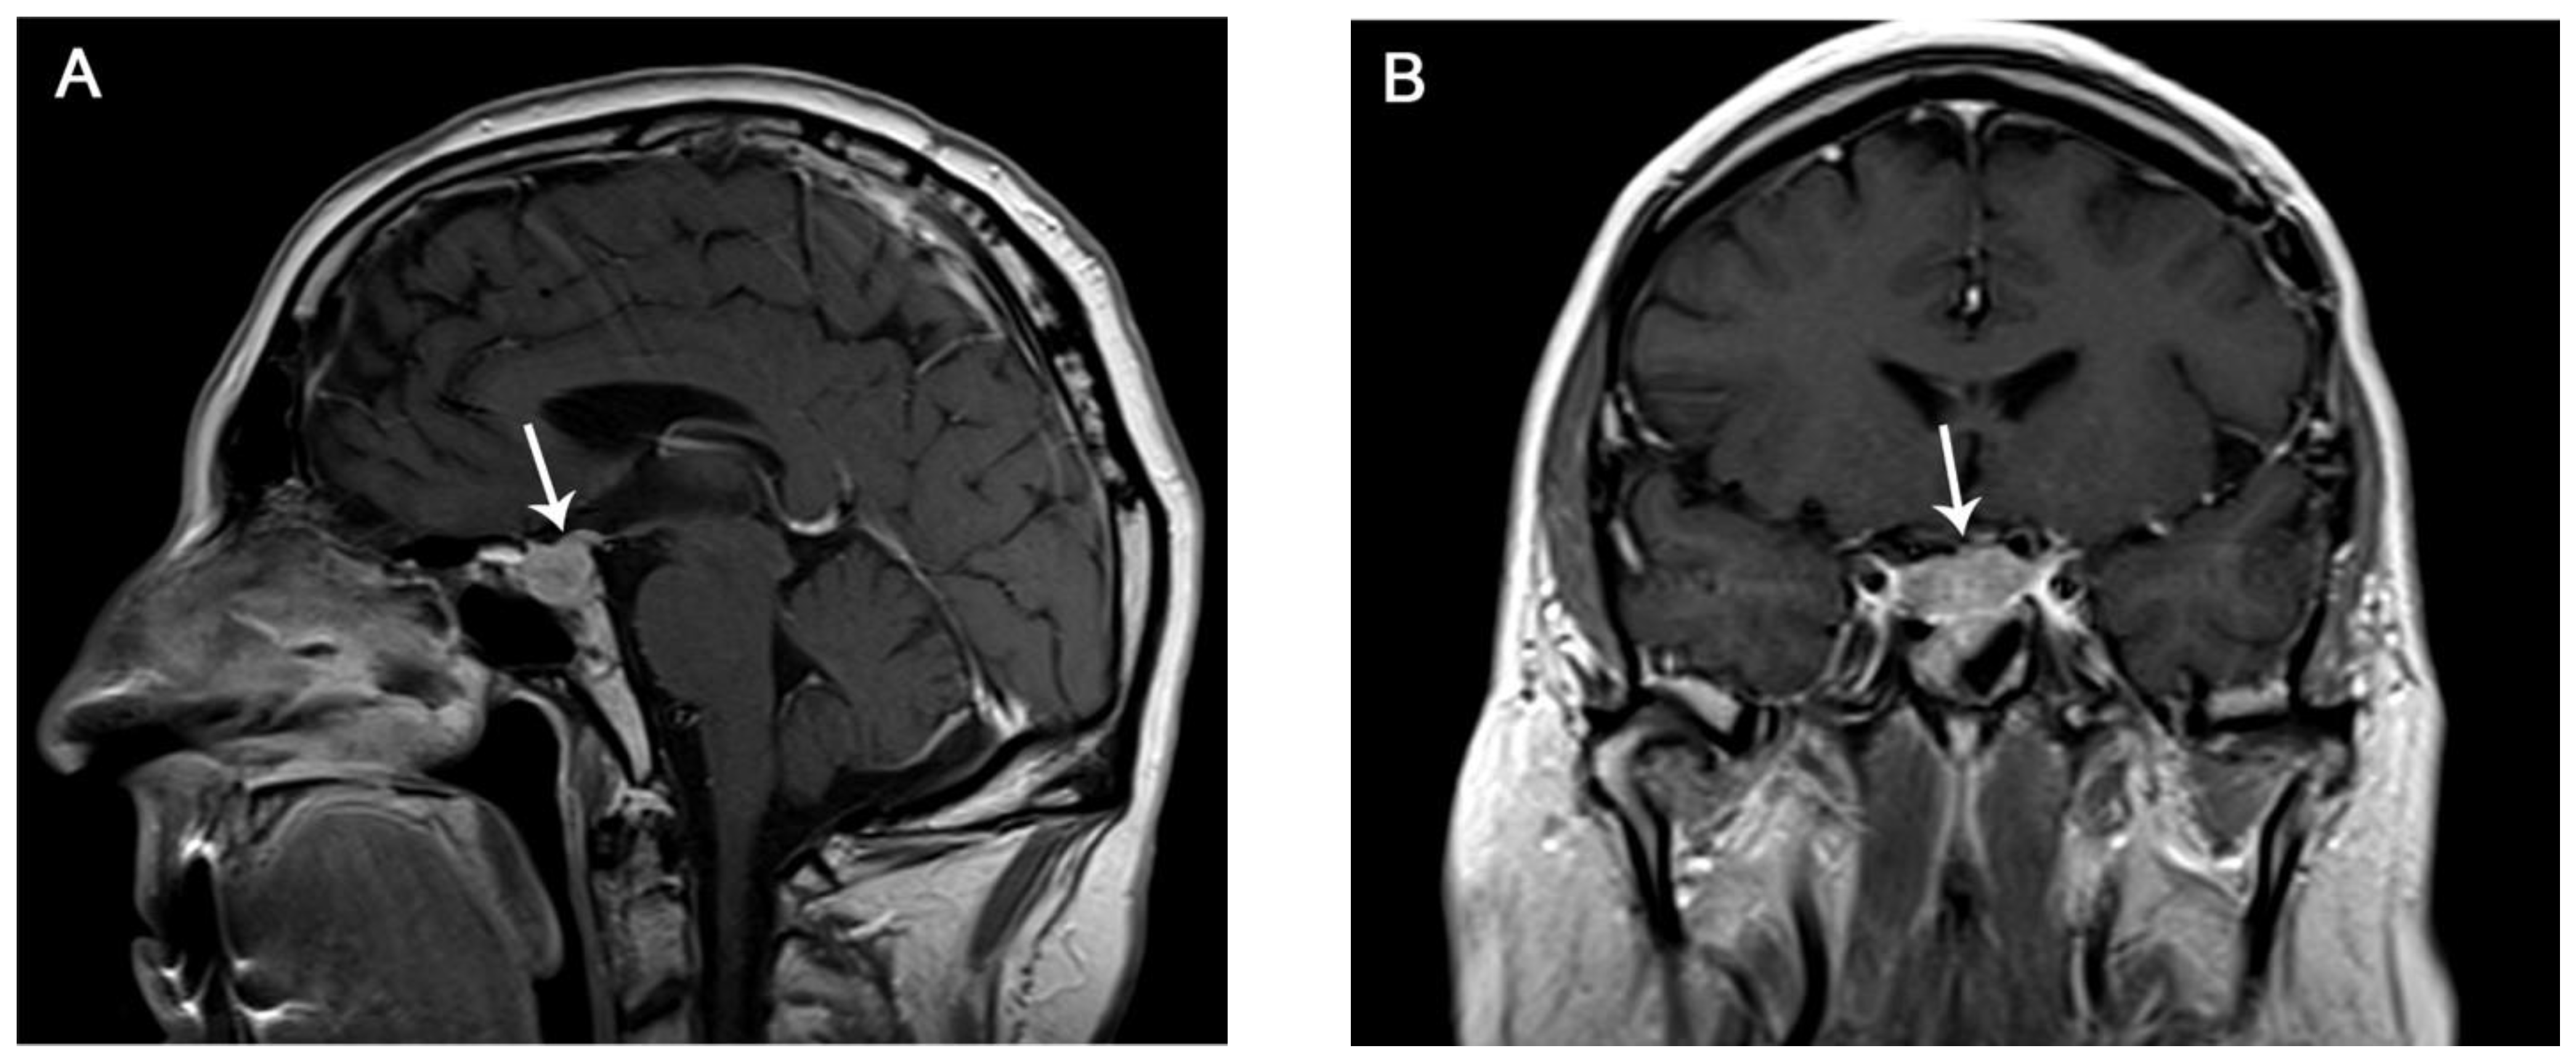

8.3. Diagnosis and Imaging

| Imaging Modality | Findings |

| CT |

| MR Necessary if suspected |

| PET-CT (18F-FDG) |

| Differential Diagnosis | Findings |

| Pituitary adenoma |

| Pituitary metastases (melanoma, breast, and lung cancer) |

| Lymphocytic hypophysitis |